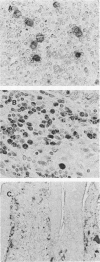

Granulomatous lesions of bovine paratuberculosis contained ferritin, lactoferrin, and a small amount of transferrin, as demonstrated by the immunohistochemical method. Macrophages in the normal bovine ileum did not contain lactoferrin and transferrin; however, ferritin was found in individual macrophages of Peyer's patches. These results may help elucidate the relationship between intracellular growth of Mycobacterium paratuberculosis and the presence of iron-binding proteins in the granulomas.